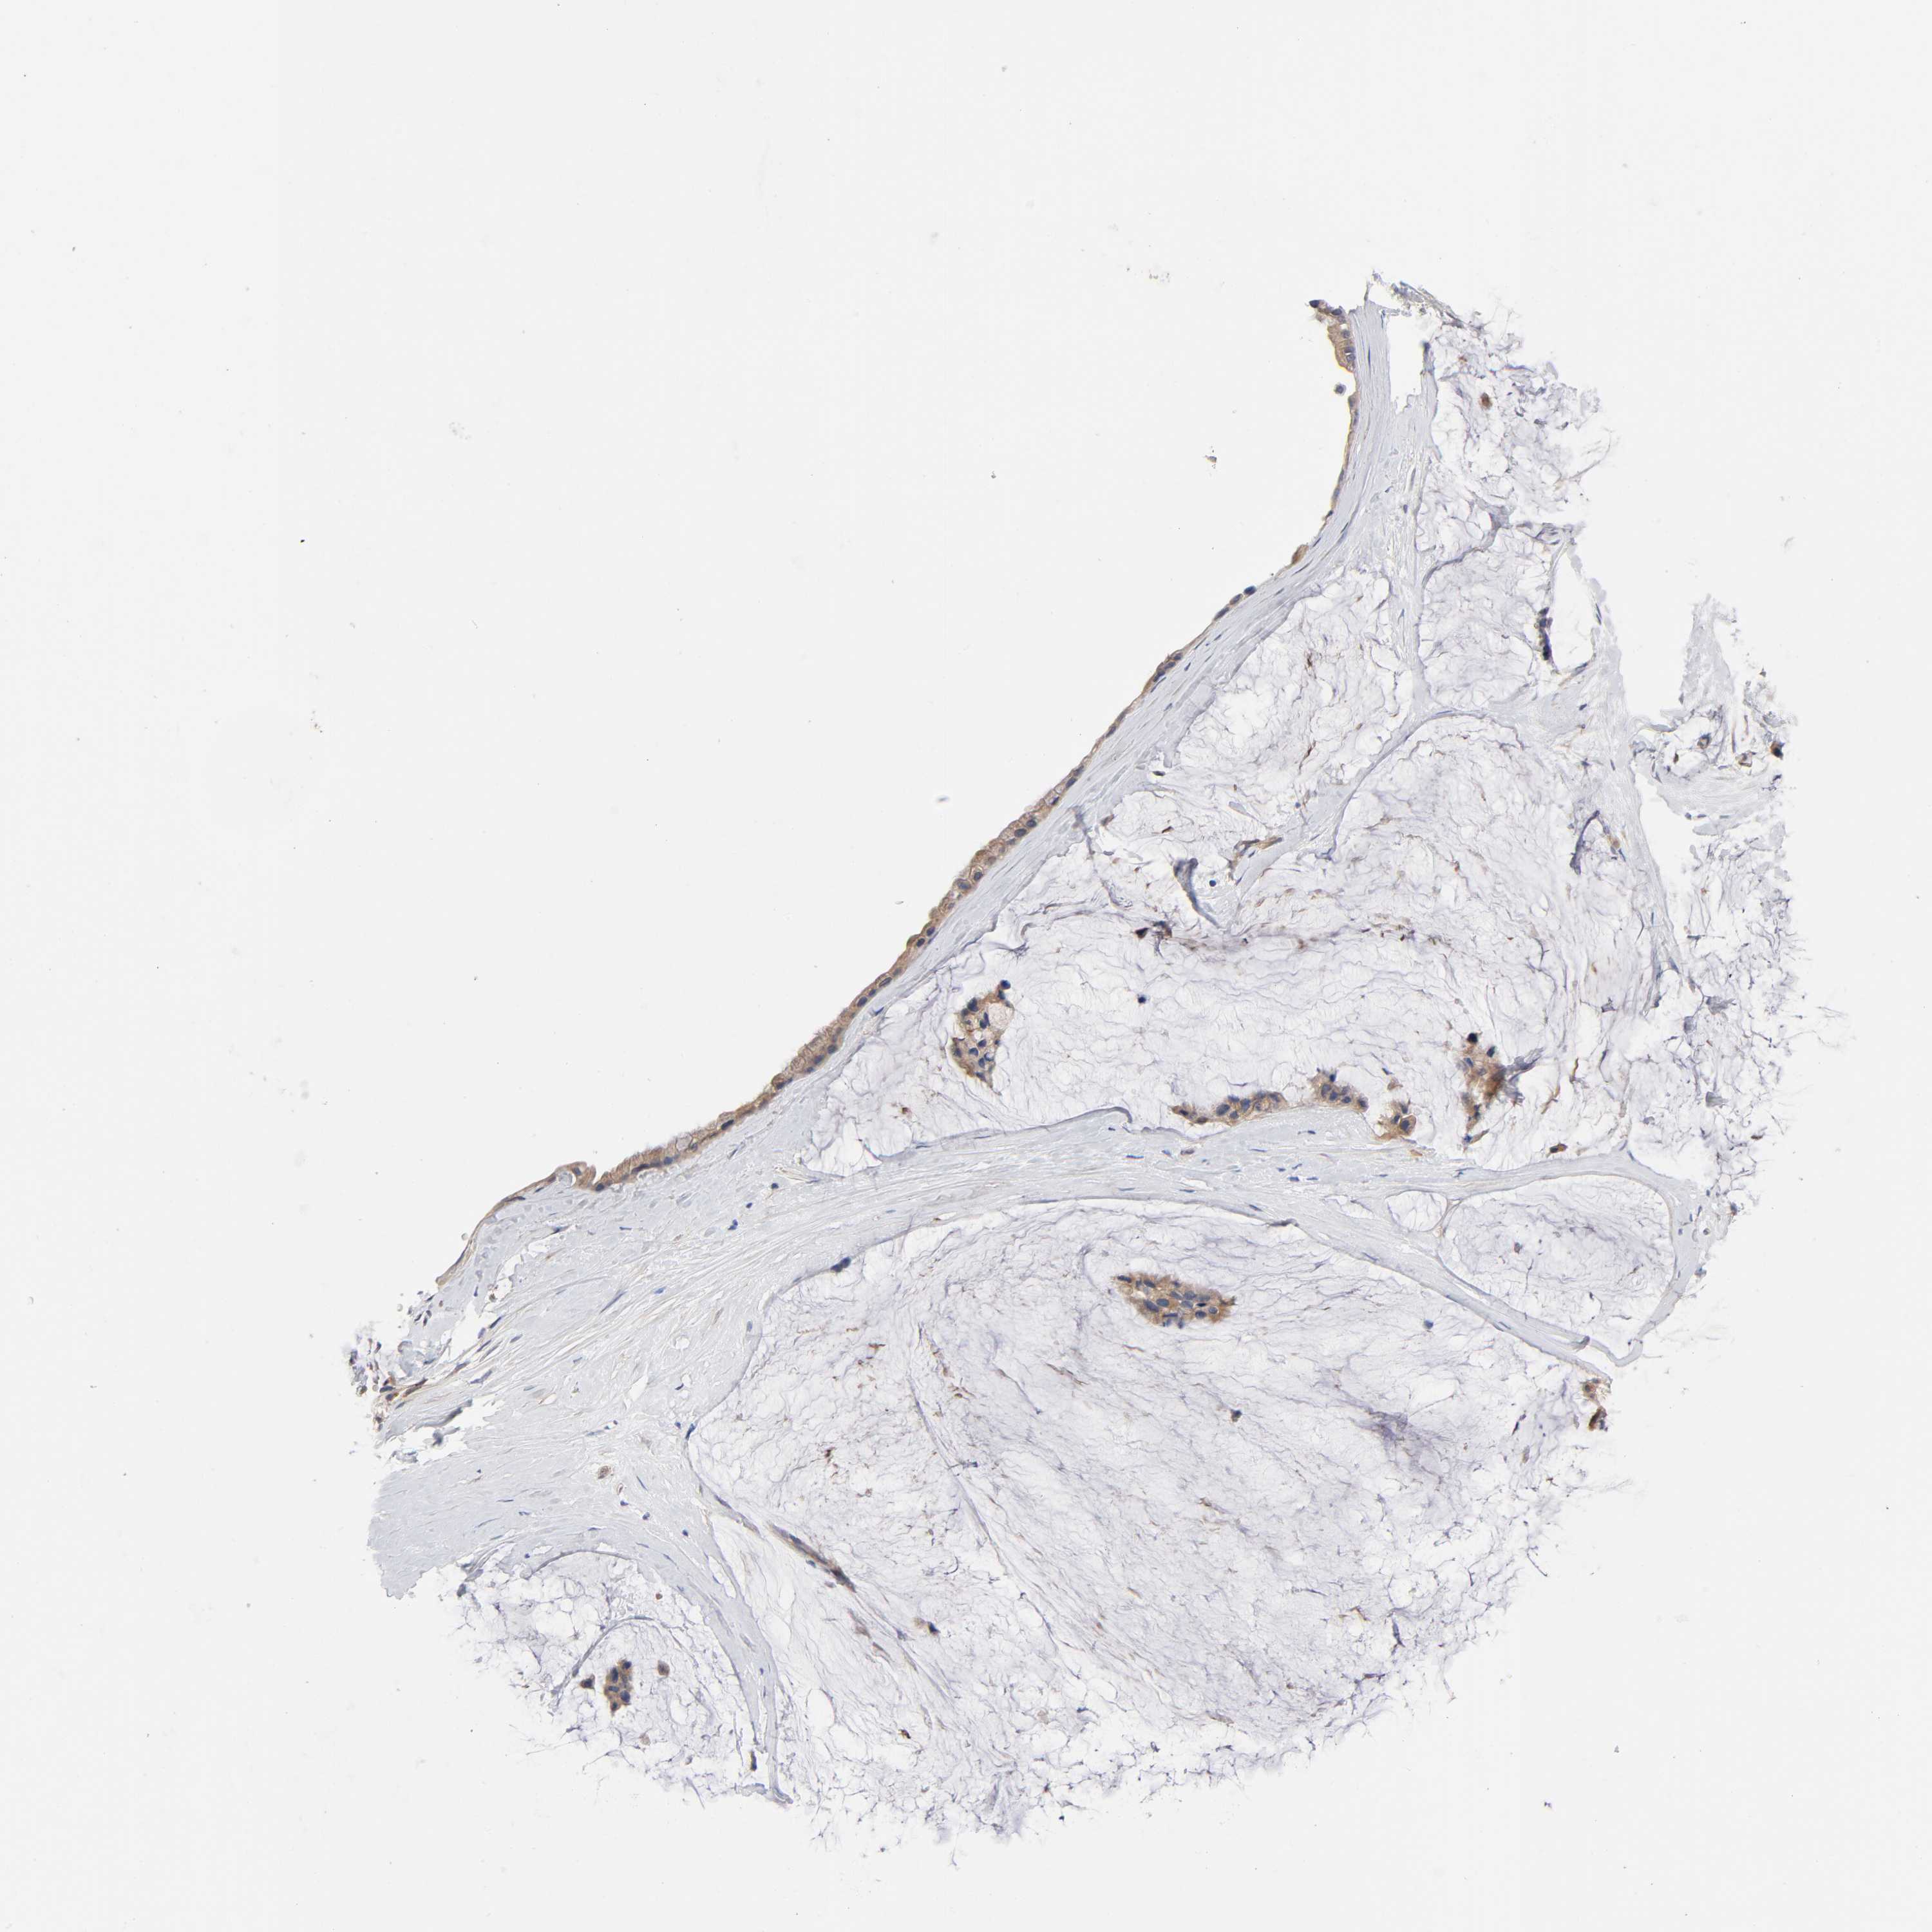

OVARIAN CANCER - Protein expressioni

A mouse-over function shows sample information and annotation data. Click on an image to view it in a full screen mode. Samples can be filtered based on level of antibody staining by selecting one or several of the following categories: high, medium, low and not detected. The assay and annotation is described here.

Note that samples used for immunohistochemistry by the Human Protein Atlas do not correspond to samples in the TCGA dataset.

Antibody stainingi

Antibody staining in the annotated cell types in the current human tissue is reported as not detected, low, medium, or high, based on conventional immunohistochemistry profiling in selected tissues. This score is based on the combination of the staining intensity and fraction of stained cells.

Each image is clickable and will lead to virtual microscopy that enables deeper exploration of all samples and also displays staining intensity scores, fraction scores and subcellular localization as well as patient and tissue information for each sample.

Antibody HPA003996

Cystadenocarcinoma, serous, NOS

Cystadenocarcinoma, mucinous, NOS

Carcinoma, endometroid